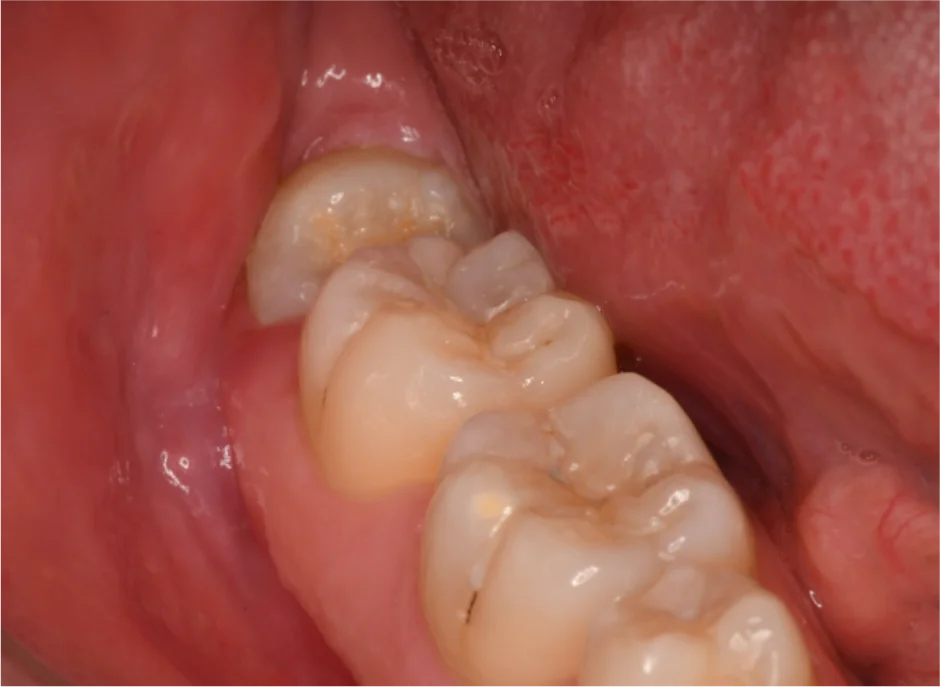

親知らずは、斜めや横向きに生えることが多く、ときには歯ぐきの炎症や痛みの原因になることもあります。

親知らずは一番奥の歯です。そのため歯磨きが難しく、虫歯や歯周病になりやすいです。 虫歯・歯周病が原因で、痛みや腫れが出てくることがあります。

また、唾液中の細菌が親知らずの周囲に感染することによって【智歯周囲炎】という病気を起こすことがあります(【智歯】=親知らず)。 この場合にも痛みや腫れをともないます。 智歯周囲炎は埋まっていない親知らずでも、上の歯との噛み合わせの刺激で起こる場合があります。

親知らずはこのように横向きに生えることが多いです。 横向きに生えた親知らずは手前の歯をグイグイと押し、歯並びに悪影響を与えることがあります。